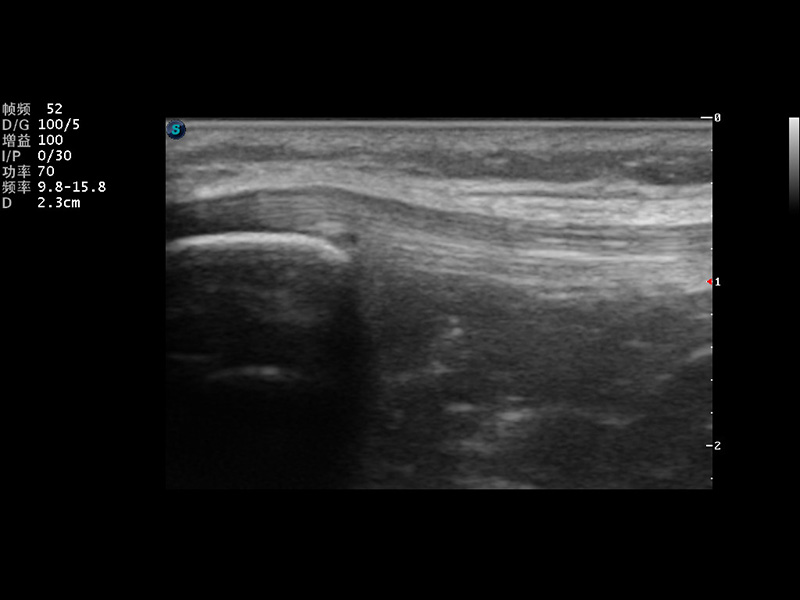

S9便携式彩色多普勒超声诊断仪是米兰官方网站研发的高端便携彩超设备,外观设计新颖、产品性能卓越。S9在便携超声领域采用了突破传统的触摸屏交互设计,并以先进的软件硬件技术和设计理念,为您带来清晰的图像质量、稳定的工作性能和便捷的操作体验。

μ-Scan微米成像